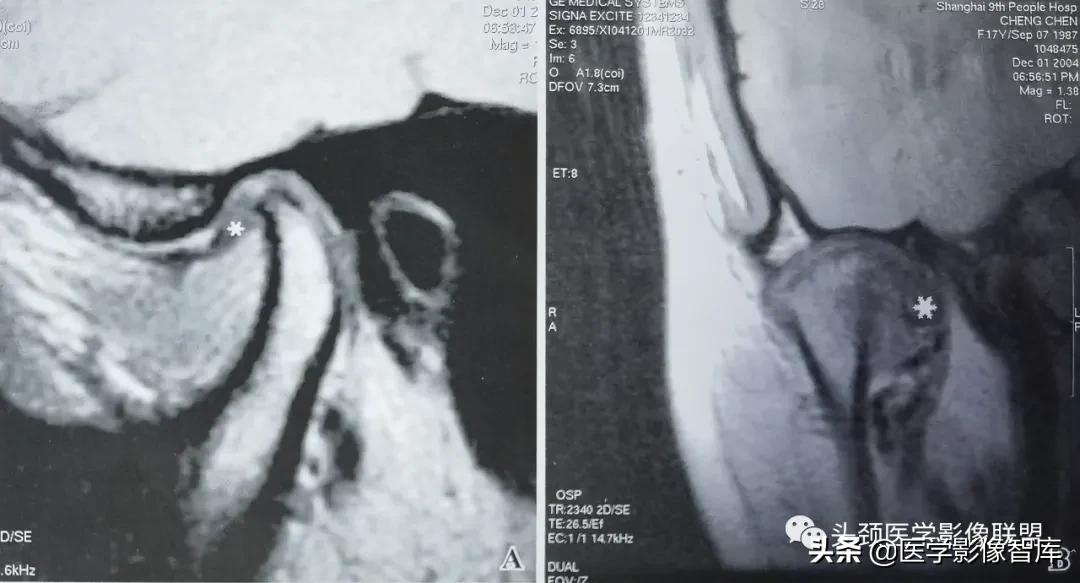

图2 不可复性关节盘前移

A. 矢状面闭口PDWI示关节盘后带(黑星)位于髁突前方;B.矢状面开口T2WI示:关节盘随下颌髁突前移,仍位于其前方。关节盘无变形,盘后附着相对拉长。关节上腔内有中量积液。下颌髁突活动度小。

不可复性盘前移位的主要临床表现为髁突活动受限。它是指闭口位时,关节盘位于下颌髁突横嵴顶的前方;张口时,随着下颌髁突向前移动,撞击关节盘后带,迫使其进一步向前移动。关节盘不能向后反跳越过髁突,因此也就不能恢复正常的盘一髁关系。不可复性盘前移位的MRI表现特点为:矢状面闭口位上 (图2A) ,低信号的关节盘明显位于髁突横嵴顶12点位的前方,关节盘后双板区被明显牵拉变长,并移位于髁突横嵴顶12点位的前方;矢状面张口位上 (图2B) ,关节盘双板区因拉伸而变直,关节盘仍位于下颌髁突的前方,不能恢复正常的盘一髁关系。

图3 不可复性关节盘前移伴盘变形

A. 矢状面闭口PDWI示:关节盘后带(黑星)位于下颌髁突前方;B. 矢状面开口T2WI示:关节盘随下颌髁突前移,仍位于其前方。开闭口位上均见关节盘呈变形改变:关节盘前带弯曲折迭,关节盘后带相对增厚。下颌髁突活动度小。

关节盘变形主要出现在不可复性盘移位中。变形的关节盘可以出现在闭口位上,也可以出现在张口之后。张口时的关节盘变形明显多见,主要是关节盘受向前运动之下颌髁突挤压所致。MRI上,变形的关节盘失去正常时双凹形或蝶结状轮廓,可以呈多样性表现,如关节盘前带弯曲折迭,关节盘后带增厚,盘后双板区纤维化和伴有盘中带缩短的盘后带增大等。由于下颌髁突在张口前移时受到前方关节盘的阻挡,故在MRI上常能显示下颌髁突活动受限。此时,下颌髁突之大部仍位于颞骨关节窝内,不能到达关节结节的下方或前下方 (图3) 。